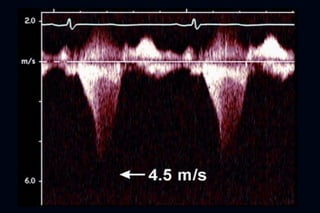

Hallazgos ecocardiográficos

   Una característica típica es el impacto del aumento del

septum en el Doppler del TSVI

   Patrón con contorno de daga

   Dagger shaped spectral Doppler pattern

   Refleja un peak tardío de flujo sistólico a través del TSVI

CW Doppler TSVI

Hallazgos ecocardiográficos  Una característica típica es el impacto del aumento del septum en el Doppler del TSVI  Patrón con contorno de daga  Dagger shaped spectral Doppler pattern  Refleja un peak tardío de flujo sistólico a través del TSVI

• #45 Figure 2. Contrasting the CW Doppler Through the Orifice of Patients With Aortic Stenosis and Obstructive HCMIn aortic stenosis the orifice remains relatively fixed in systole. In hypertrophic cardiomyopathy (HCM) obstruction begets more obstruction, and the orifice narrows through systole. The left ventricular ejection is unobstructed in early systole, and the curve is convex-to-the-left. At the inflection point (long arrow) , mitral-septal contact and obstruction begin. The orifice narrows because of the rising pressure difference; the pressure difference rises because of the decreasing orifice size—an amplifying feedback loop. Hence, the contour shows an increasing acceleration pattern: it is concave-to-the-left (arrowheads) . CW = continuous wave. Adapted, with permission, from Sherrid et al. The amplifying nature of outflow obstruction has significance for the therapy of symptomatic gradients. The longer in systole that the gradient acts, and the longer the duration of mitral-septal contact, the higher the gradient. Successful therapy abolishes or delays SAM (6). The amplifying nature of outflow obstruction also may explain the dramatic changes in gradient that occur with loading conditions, and may explain the sometimes explosive emergence of severe outflow obstruction in the elderly.

• #46 Figure 7 Typical continuous wave Doppler recording from a patient with dynamic LVOT obstruction in the setting of hypertrophic obstructive cardiomyopathy. Note the dagger-shaped profile. (Reproduced with permission from Oh et al. &lt;ce:cross-ref re...

• #47 Figure 1 CW Doppler Echocardiographic Tracing Through the Obstructing Orifice in the LVOT of a Patient With a Gradient of 64 mm Hg The inflection point is shown with a long arrow and the concave-to-the-left contour is shown with arrowheads . ...